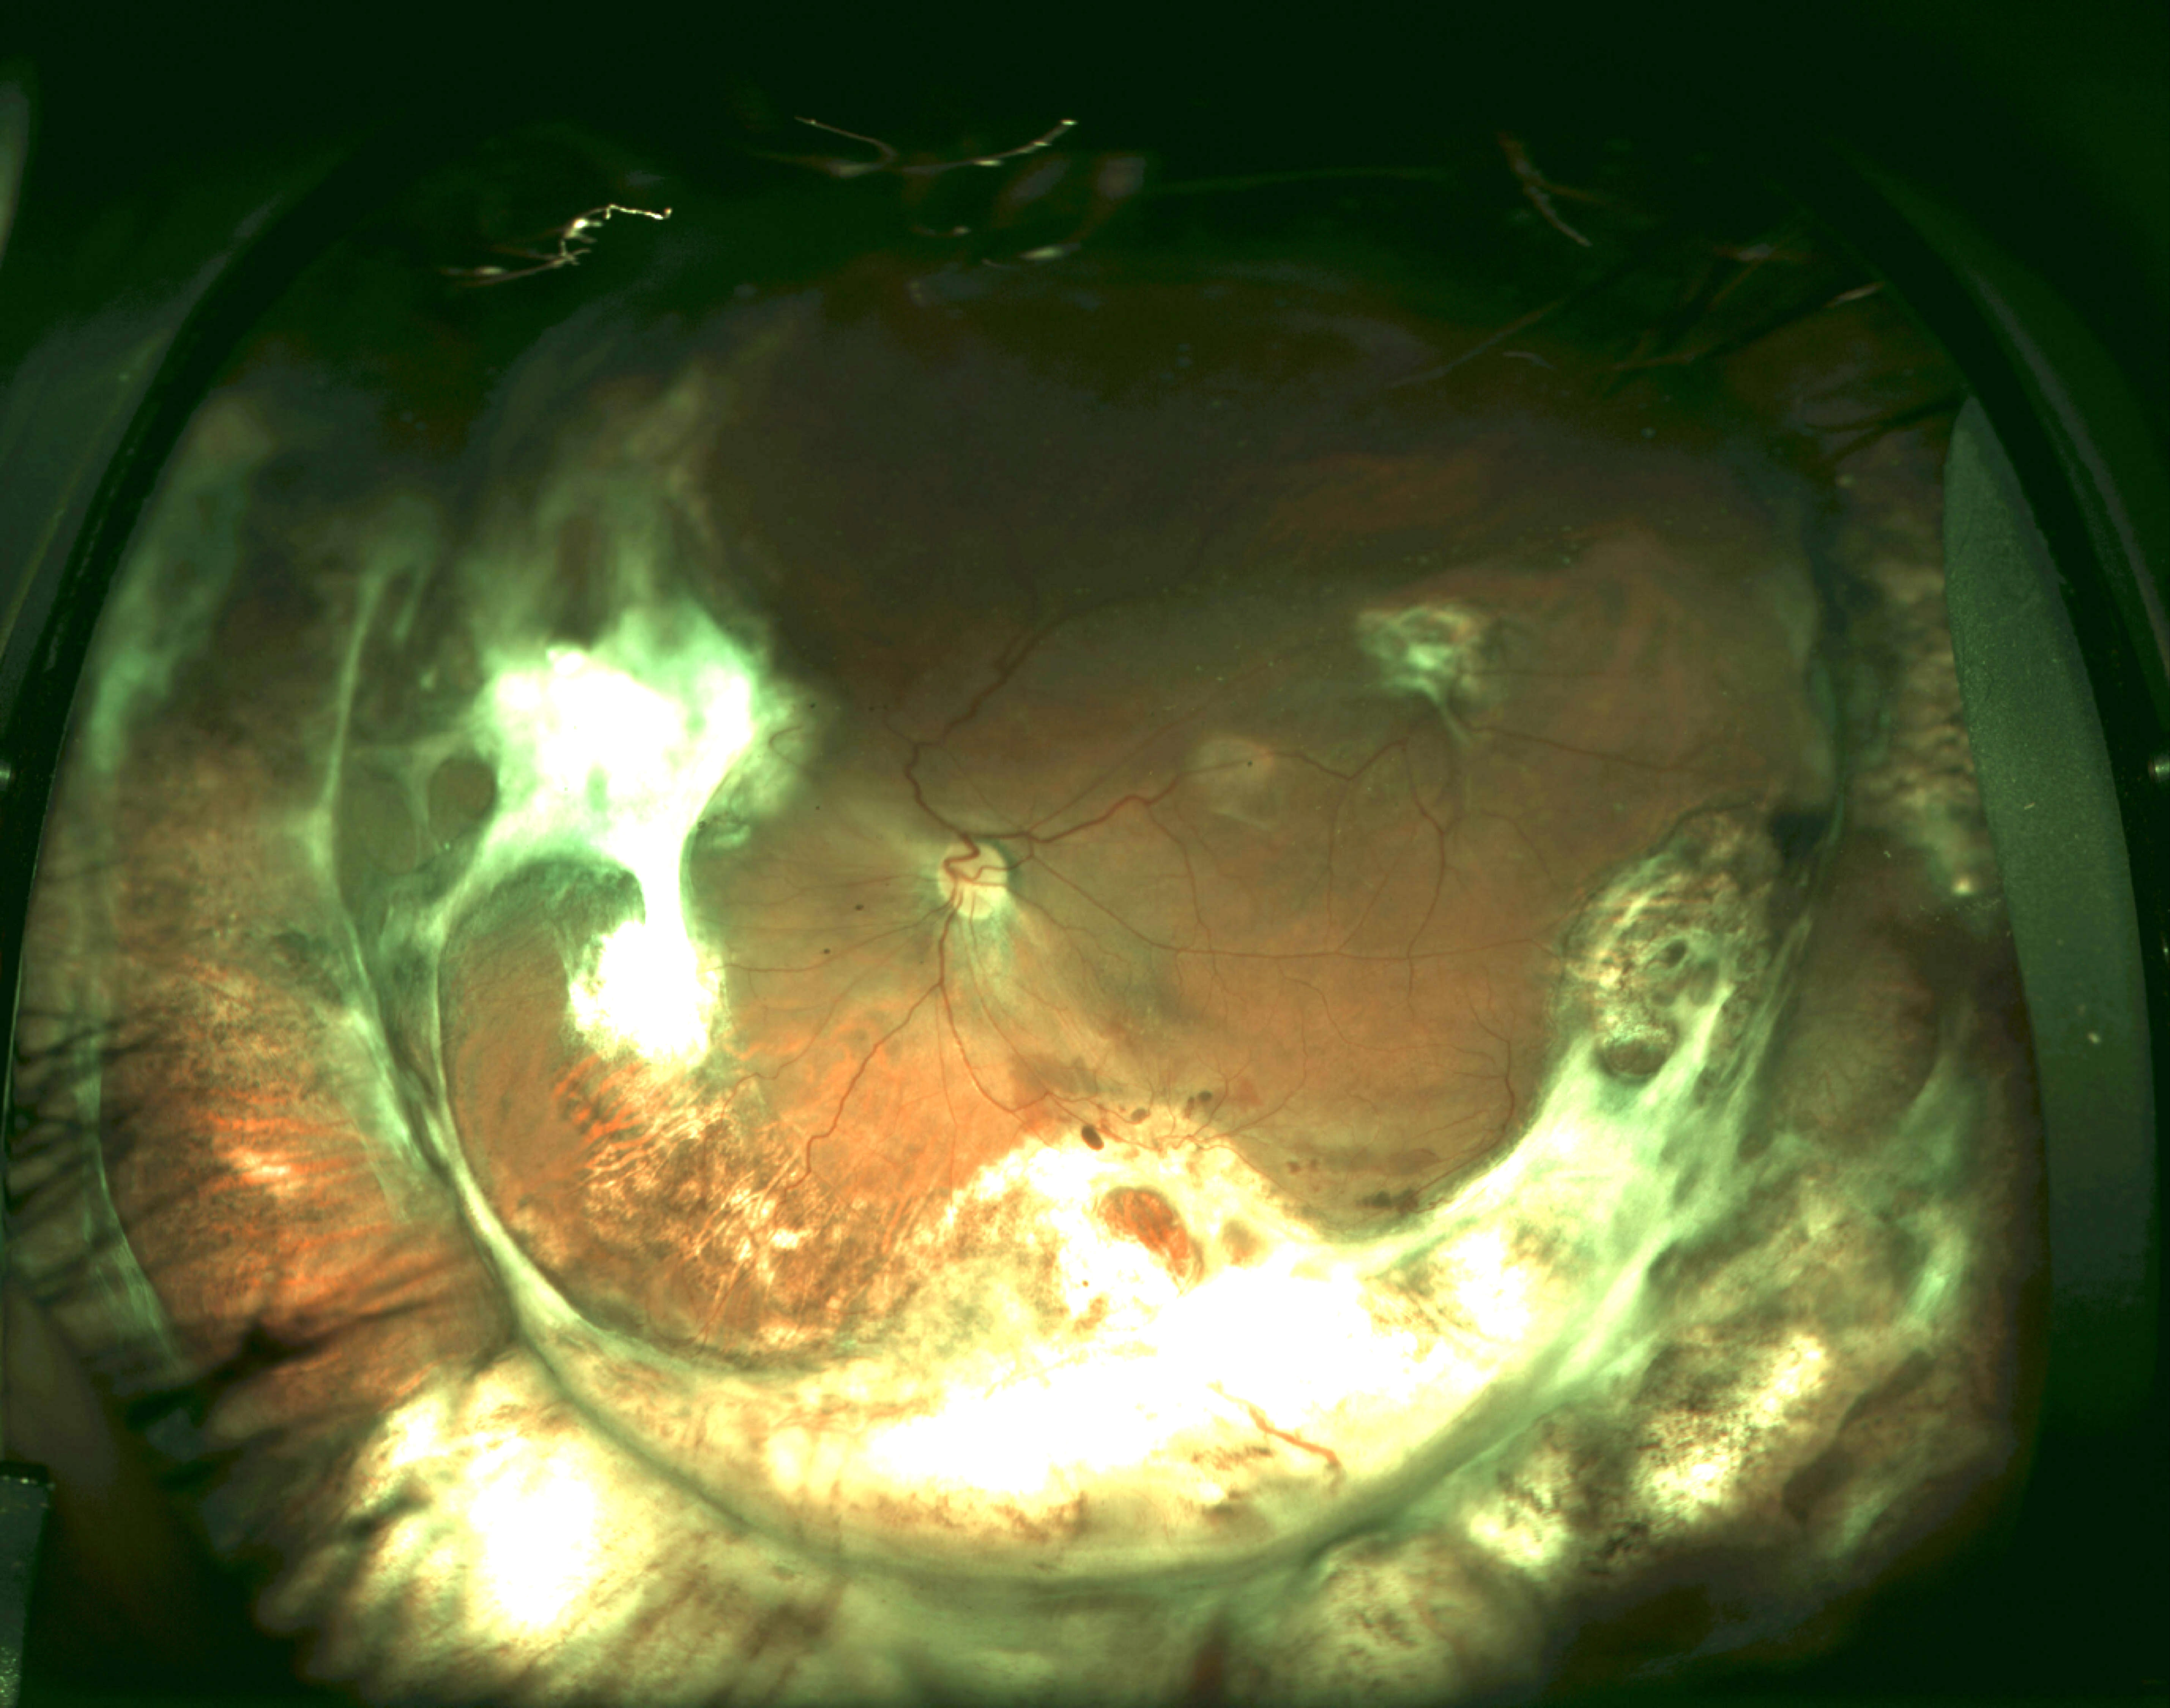

Interestingly, Dr. Kim’s team used an intravitreal injection of human-derived PVR cells in a rabbit model to study PVR formation. A few weeks subsequent to intravitreal injection, fundus examination demonstrated focal areas of traction and optical coherence tomography demonstrated clumps of fibroglial cells overlying the optic nerve and retinal surface which eventually formed sheets of preretinal fibrovascular tissue. After developing the animal model, he demonstrated that RUNX1 and rho-kinase inhibition both resulted in diminished EMT and thereby decreased PVR formation. Explant models showed similar findings. Dr. Kim’s research potentially implicates RUNX1 and rho-kinase as molecular targets to help prevent PVR formation. We look forward to further developments by his team.